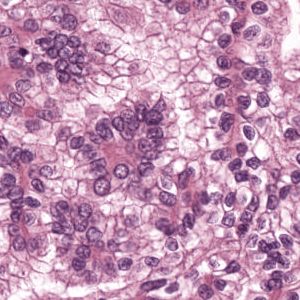

As an essential part of digital pathology, histopathology image analysis is playing increasingly important role in cancer diagnosis, which can provide direct and reliable evidence to diagnose the grade and type of cancer. This paper deals with nuclei segmentation, an important step in histopathological image analysis. The purpose of nuclei semgentation is not only counting the number of nuclei but also obtaining the detailed information of each nucleus. So unlike nuclei detection, here the outputs are the contour of each nucleus instead of only the position of their central points. Hence we can exactly extract each nucleus from the image and make it available for further analysis. For example, the features of the individual nucleus and the distribution of nuclei clusters can be used to grade and classify status of breast cancers [3, 4]. Because of appearance variation such as color, shape, and texture, nuclei segmentation from histopathological images could be very challenging, as illustrated in Fig.1, in which it is very challenging even for human to recognize and segment all nuclei within the images. Fig.1(a) and Fig.1(b) illustrate two histopathological images from different organs. Fig.1(c) and Fig.1(d) are two histopathological images from same organ but have different cancer grade.

H&E stain is the most widely used stain protocol in medical diagnosis. Typically, the nuclei of cells are stained to blue by Haematoxylin while cytoplasm is colored to pink by Eosin. But in practice, the color of H&E stained images could vary a lot due to variation in the H&E reagents, staining process, scanner and the specialist who performs the staining, as shown in Fig.1. A few H&E stain normalization methods[23, 24, 25] have been proposed to eliminate the negative interference caused by color variation. We tried two of them[23, 25] to normalize the raw H&E stained images. For our segmentation algorithm, we did not find any considerable difference between these two normalization methods. Particularly, the result shown in experiment section III is generated based on the images normalized by the method in [23]. Given a target image, this method is able to convert one image’s color into the target image’s color space based on sparse non-negative matrix factorization(NMF). We choose one best stained H&E image as the target and convert other images into its color space. According to the recommendation in [23], the hyper-parameter should be set between 0.01 and 0.1. In our experiment, is set to 0.1.